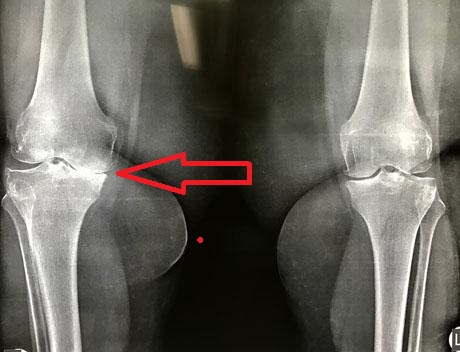

Pre-op X-ray, severe osteoartrhitis of the knees bilaterally (final stage – bone to bone contact)

Varus deformity of the right knee, which reaches 17.9 degrees without weight bearing the right lower limb

Pre-op X-rays. Severe degenerative osteoarthritis of the knees with varus deformity

Pre-op X-ray. Severe knee osteoarthritis bilaterally

Pre-op X-ray. Valgus deformity of the knees

Electronicaly measurement of valgus deformation in valgus preoperative with Patient Spesicic Instruments System. Without weight bearing of the left lower limb the angle exceeds 10 degrees